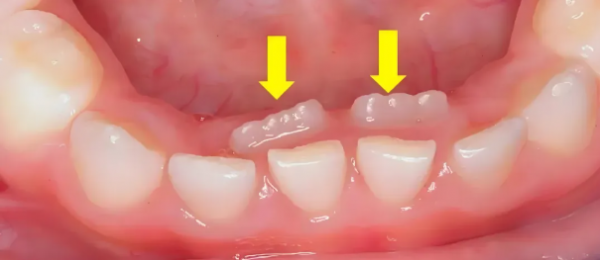

正常情況下,孩子的乳牙會(huì)在6-12歲期間逐漸脫落,為恒牙讓出位置。當(dāng)乳牙尚未脫落,而恒牙已經(jīng)從牙齦內(nèi)側(cè)或外側(cè)萌出時(shí),就形成了“雙排牙”。

這種現(xiàn)象最常見于下前牙區(qū)域,其次是上前牙區(qū)域。數(shù)據(jù)顯示,近年來兒童雙排牙的發(fā)病率顯著上升,已成為兒童口腔科的常見問題。